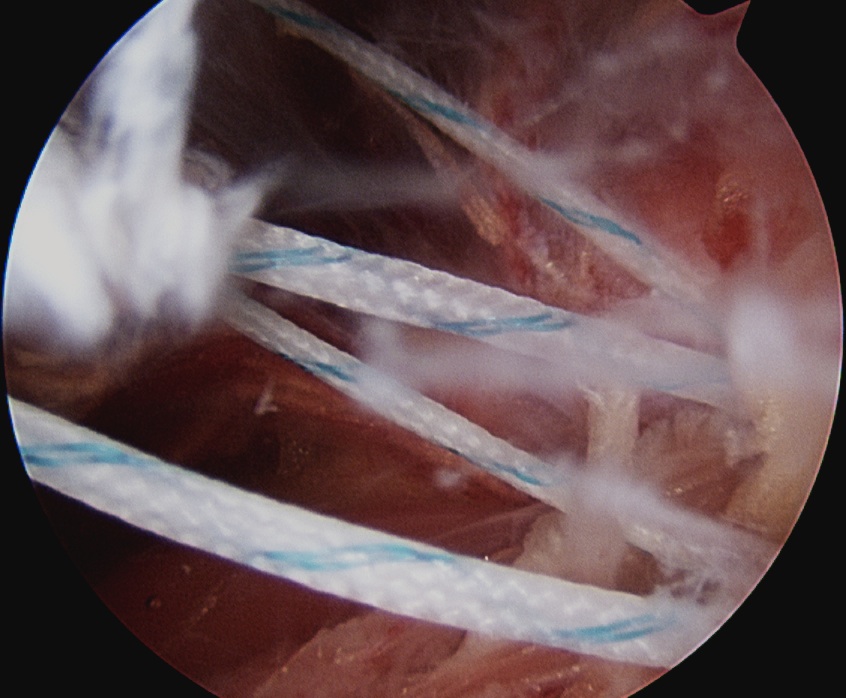

Anchor insertion into Hill Sachs lesion